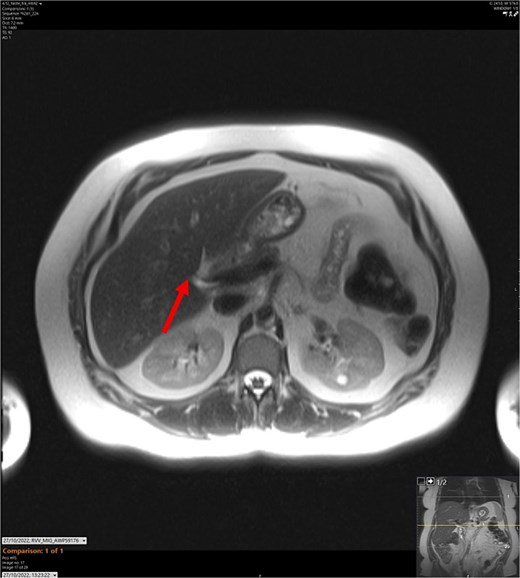

T2-weighted MRCP scan in axial view. The arrow points to where we expect the gallbladder to be seen, but it cannot be visualized on the scan.